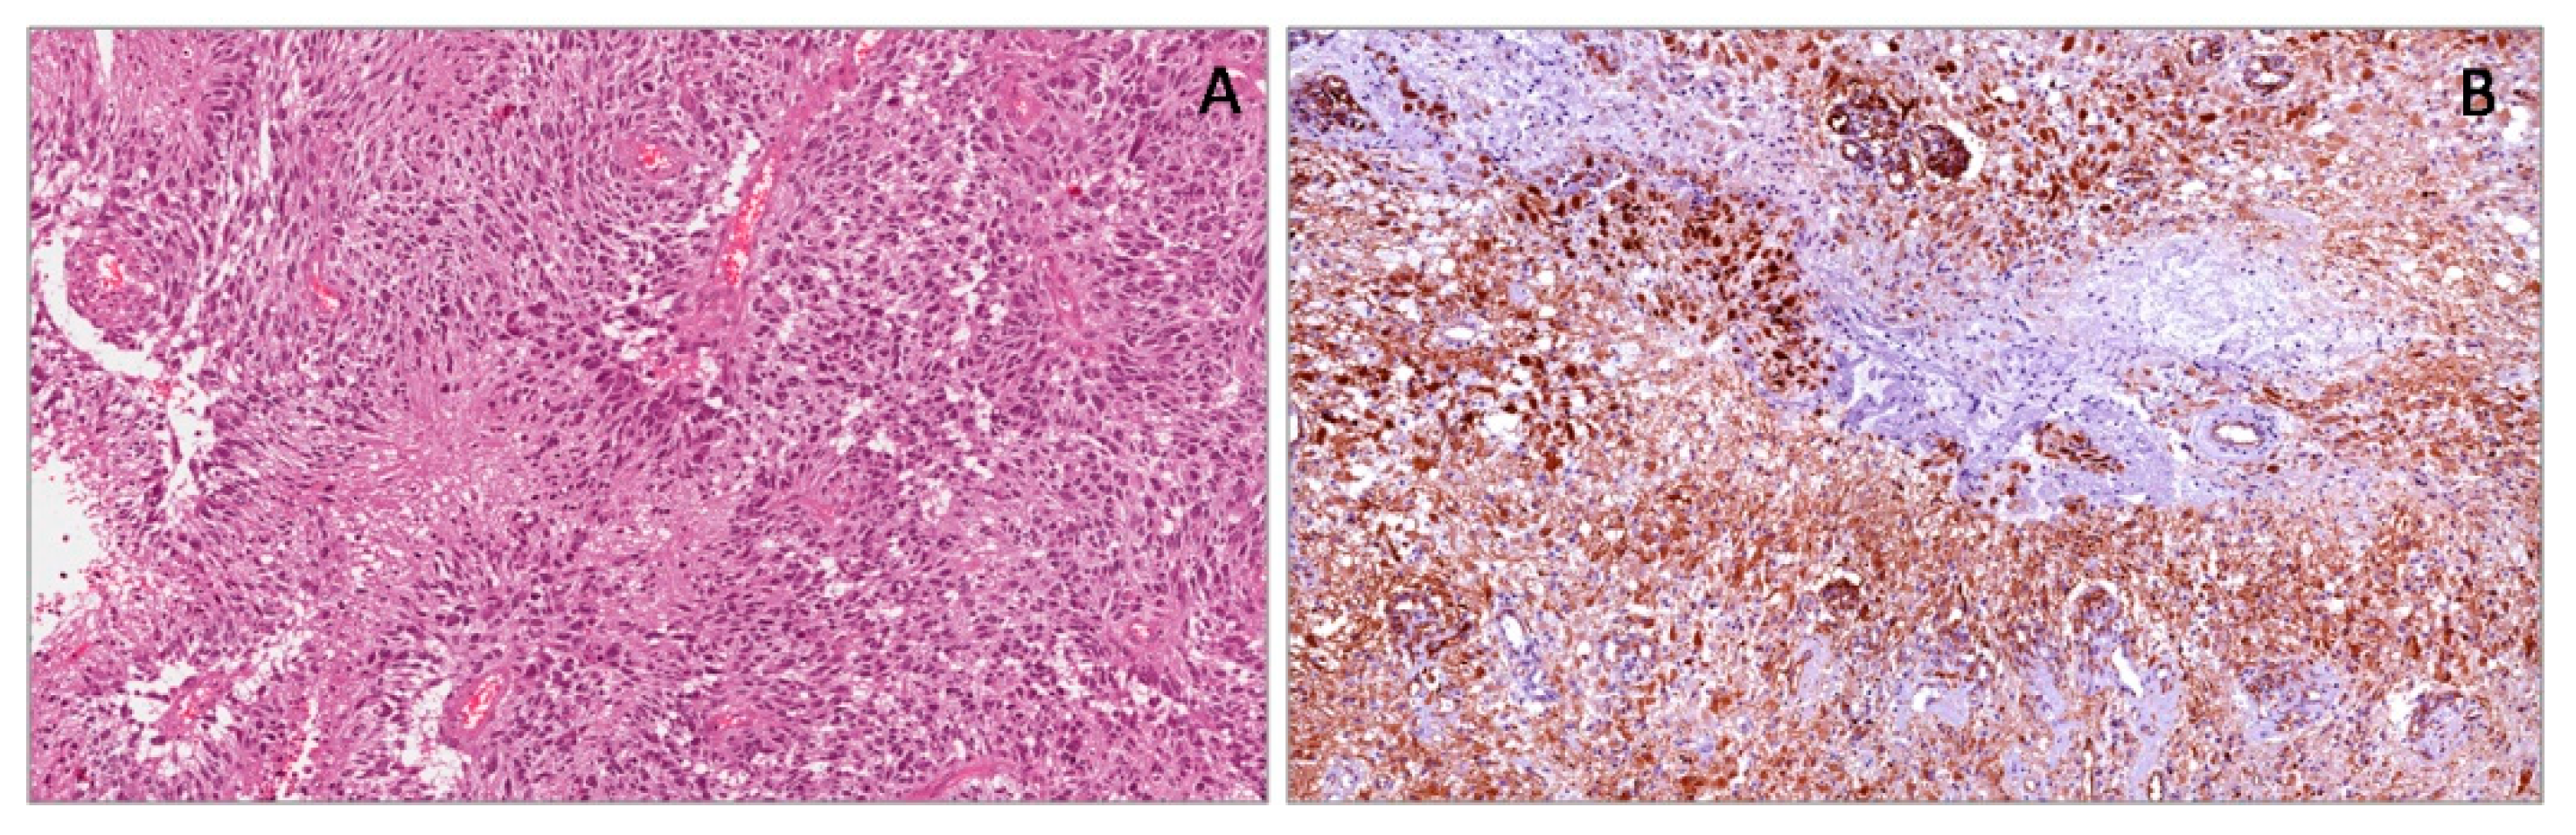

2.3. Malignant Mesothelialioma